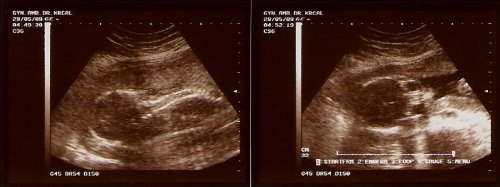

6.3.09 - krev dopadla na výbornou, všechno v pořádku, jsme 12tt+4 podle ultrazvuku ... jinak pan doktor chválil, jak skvěle rosteme a maminka ani nepřibírá 🙂

22.5.2009 - všechno je v pořádku, testy vychází velmi dobře. Dneska nám pan doktor řekl, že čekáme holčičku 🙂 Tak jsme oba moc rádi ... 8.6. nás čeká 4D ultrazvuk a kontrola další 19.6.